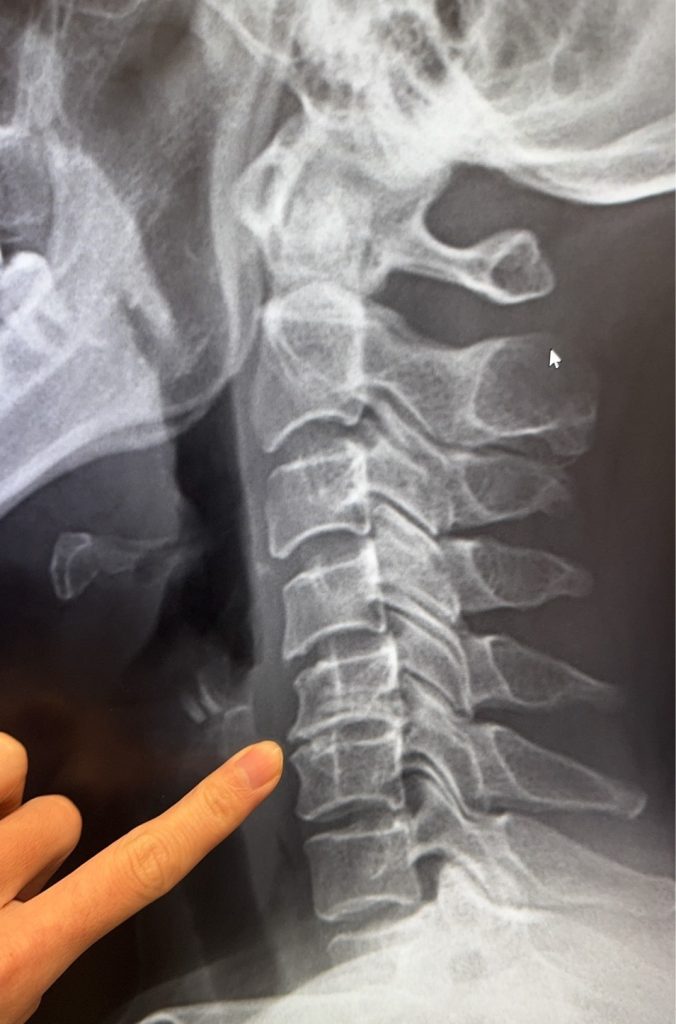

(陳建宏骨科診所提供)

以頸椎為例,現在人低頭滑手機,每天讓頸椎承受超過10幾公斤往前拉的力量,肌肉撐不住,就會把頭部的壓力丟給頸椎關節,時間久了,關節為了保護自己,才會長出骨刺。因此,比起害怕骨刺,更應該在意的是患者的生活方式。那些彎腰駝背、不正確的姿勢負重,及一整天不動的習慣,比任何骨刺都更能決定脊椎健康。